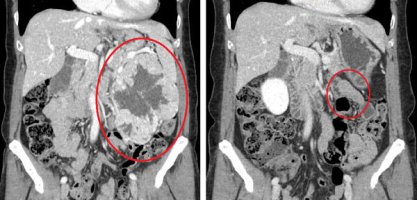

신장암의 대표적인 증상으로는 옆구리 통증, 혈뇨, 배에 덩어리가 만져지는 것이다. 또 호흡곤란, 기침, 발작, 두통, 뼈의 통증, 고혈압, 간 기능 이상 등 부종양 증후군이 나타날 수 있다.종양의 크기가 작을 때는 대부분 증상이 없다. 증상이 나타나는 경우는 이미 종양의 크기가 커져 주위 장기를 압박하고 있으며, 첫 진단 시 30% 정도는 이미 전이된 상태다.

이 신장에 발생한 악성 종양을 신장암이라고 부른다. 신장암은 발생 위치에 따라 신우암과 신세포암으로 구분된다. 신장암에서 발생하는 암의 85%는 신세포암이다.

만약 다른 장기에 전이가 있거나 재발의 위험이 높은 신장암의 경우에는 수술적 치료와 함께 표적 치료, 면역 요법을 함께 시행하는 경우도 있습니다. 다발성 전이로 수술 치료가 도움이 되지 않다고 판단되는 경우는 표적 치료, 면역 요법만 시행하는 경우도 있습니다. 신장암의 완치를 위해서는 철저한 수술적 치료가 반드시 필요하며, 다른 장기로의 전이가 없는 신장암의 경우에는 개복 또는 복강경 등을 이용한 신장 적출 또는 부분 절제술을 시행합니다.